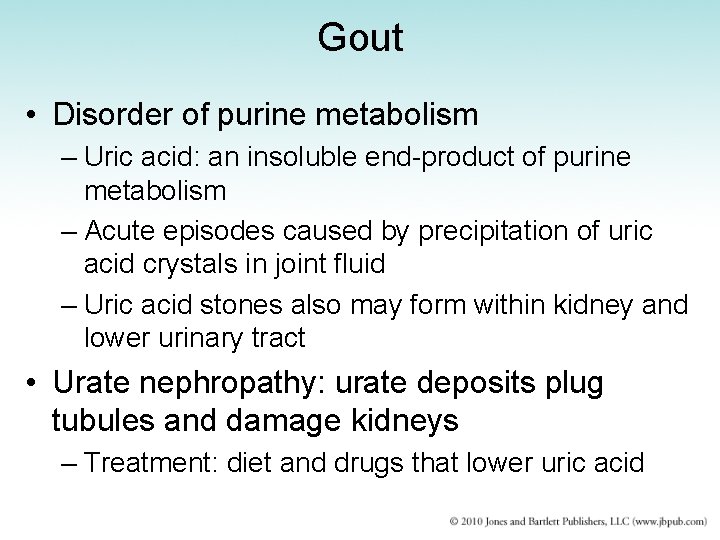

Gout • Disorder of purine metabolism – Uric acid: an insoluble end-product of purine metabolism – Acute episodes caused by precipitation of uric acid crystals in joint fluid – Uric acid stones also may form within kidney and lower urinary tract • Urate nephropathy: urate deposits plug tubules and damage kidneys – Treatment: diet and drugs that lower uric acid